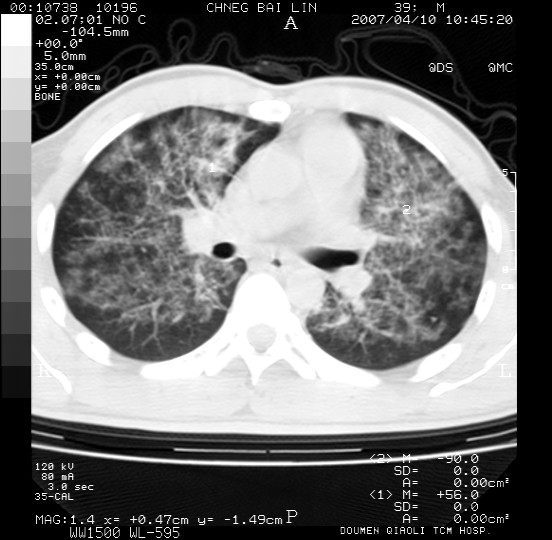

男,39岁。10天前自觉感冒,曾输液一次内容不详曾有吸毒史。现有咳嗽、咳痰胸闷。

双肺弥漫性网状、磨玻璃样病灶,边界不清。有吸毒史。首先考虑机遇性肺部感染。

双肺野蜂窝状结构及多发斑片状影,高度怀疑卡氏囊虫性肺炎

两肺弥漫分布的网状毛玻璃状阴影,边缘模糊不清,纵隔未见明显淋巴结肿大

诊断:机遇性肺部感染

鉴别诊断:1特发性肺纤维化,主要部位在两肺下叶胸膜下网状,毛玻璃状及蜂窝状阴影,临近胸膜增厚,该病征象不太符合